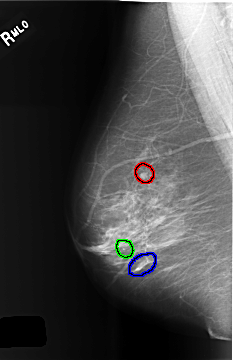

C_0508_1.RIGHT_MLO

FILE: C_0508_1.RIGHT_MLO.OVERLAY

TOTAL_ABNORMALITIES 3

ABNORMALITY 1

LESION_TYPE MASS SHAPE ROUND MARGINS CIRCUMSCRIBED

ASSESSMENT 2

SUBTLETY 5

PATHOLOGY BENIGN_WITHOUT_CALLBACK

TOTAL_OUTLINES 1

BOUNDARY

ABNORMALITY 2

LESION_TYPE CALCIFICATION TYPE PLEOMORPHIC DISTRIBUTION CLUSTERED

ASSESSMENT 3

PATHOLOGY BENIGN

ABNORMALITY 3

ASSESSMENT 4

TOTAL_OUTLINES 2